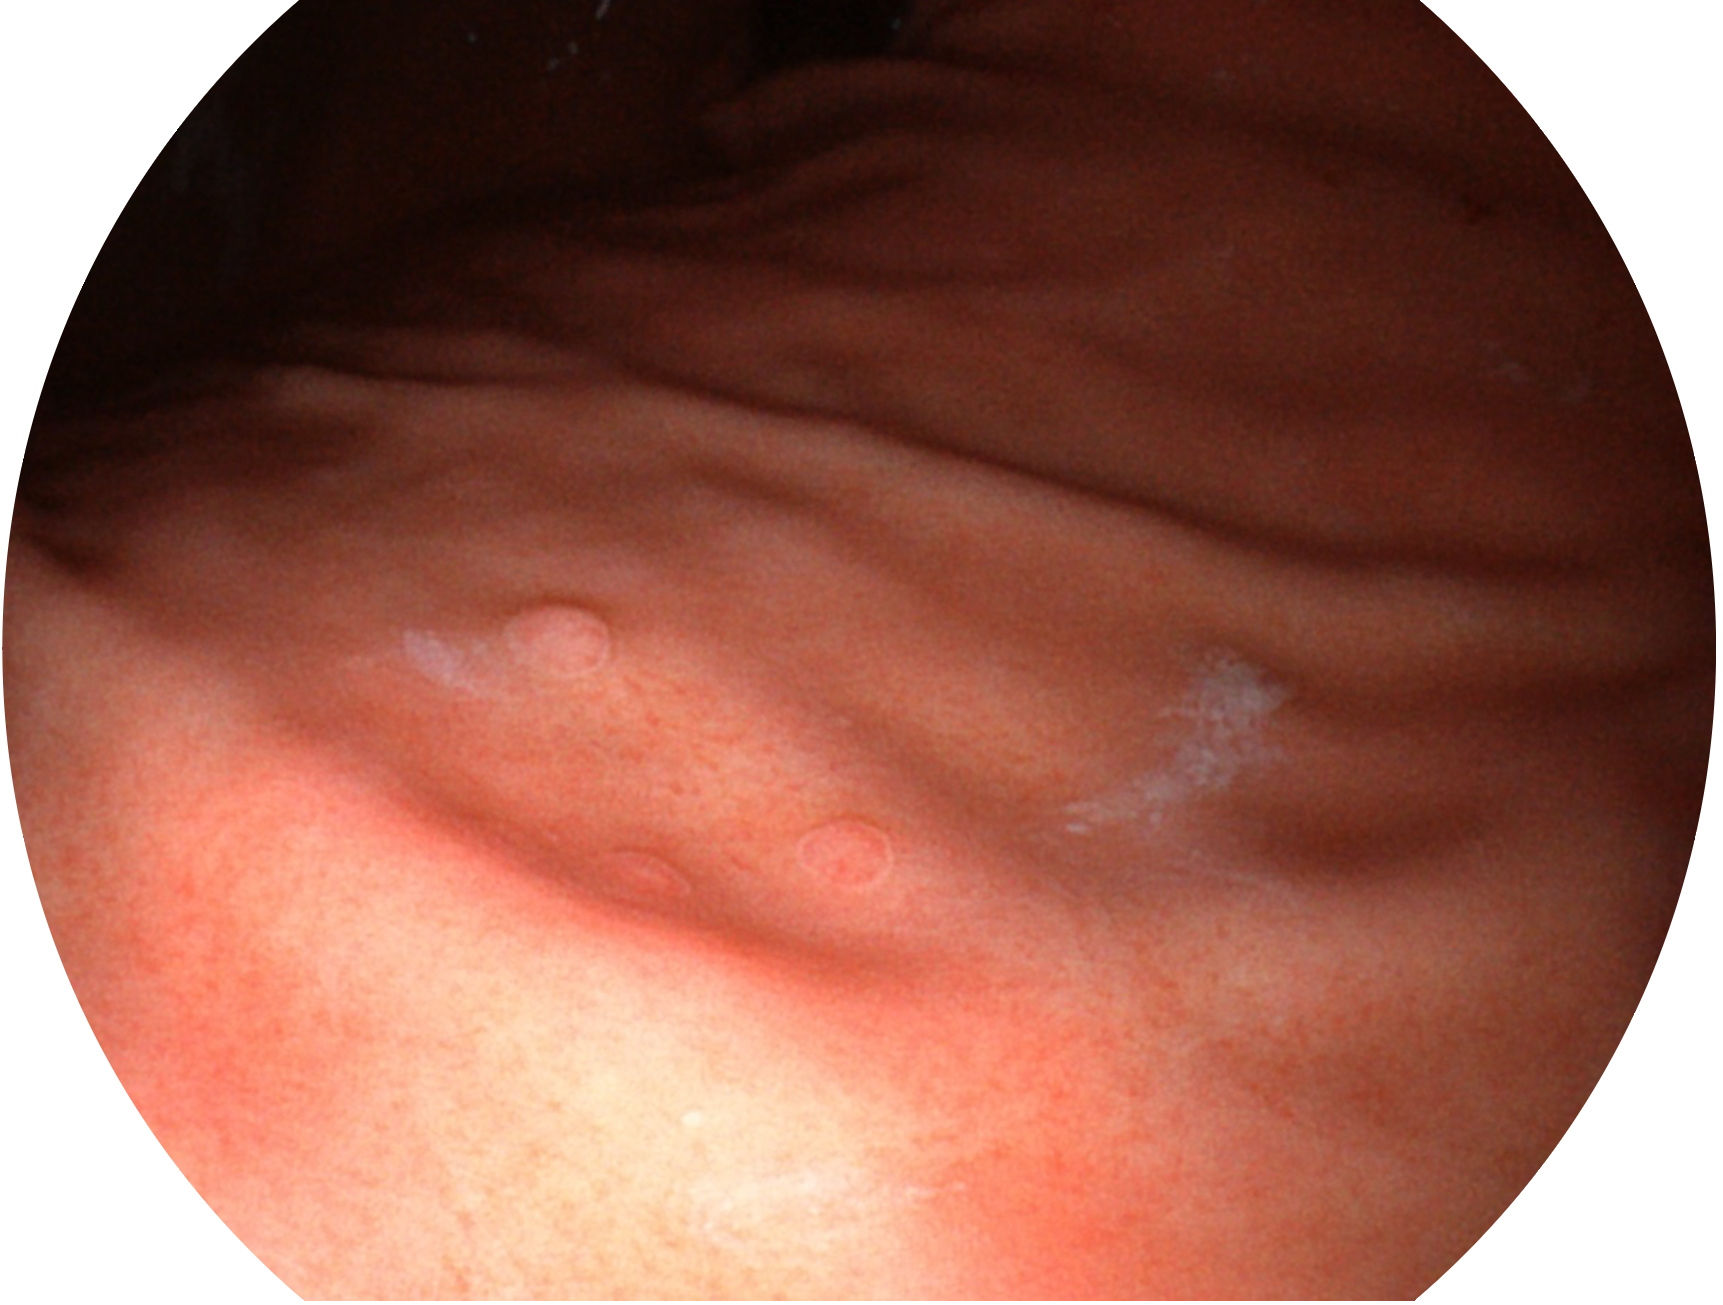

与上一代VIST相比,摒弃了滤光转轮而直接采用光谱组合的方案,加入了血红蛋白吸收高峰与次高峰的蓝紫光和绿光光谱,更有利于黏膜血管吸收,突显浅表层血管和中层血管的对比度,因而具备更高的图像对比度,近景观察时,有助于微细结构变化及病灶边界的观察。

• 白光图像 VIST图像